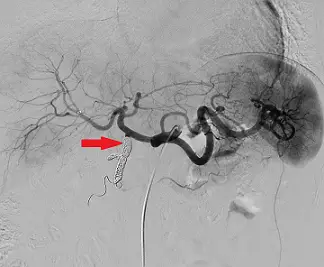

附圖為肝臟血管攝影,圖中紅色箭號所指已栓塞血管為下列何者?

- 影像模式:這是一張數位減影血管攝影(Digital Subtraction Angiography, DSA)影像。

- 導管位置與主幹:導管由下方進入並置放於 Celiac trunk 或 Common hepatic artery 進行對比劑注射。

- 畫面右側(病人解剖學左側)可見走向彎曲且朝向脾臟的 Splenic artery。

- 畫面左側(病人解剖學右側)可見主幹朝向肝臟,此為 Common hepatic artery。

- Common hepatic artery 在行進過程中會產生一個向下(Inferiorly)的分支,即為 Gastroduodenal artery (GDA)。

- 在分出 GDA 之後,主幹繼續向上方延伸進入肝門,稱為 Proper hepatic artery,隨後再分支為 Right hepatic artery 與 Left hepatic a